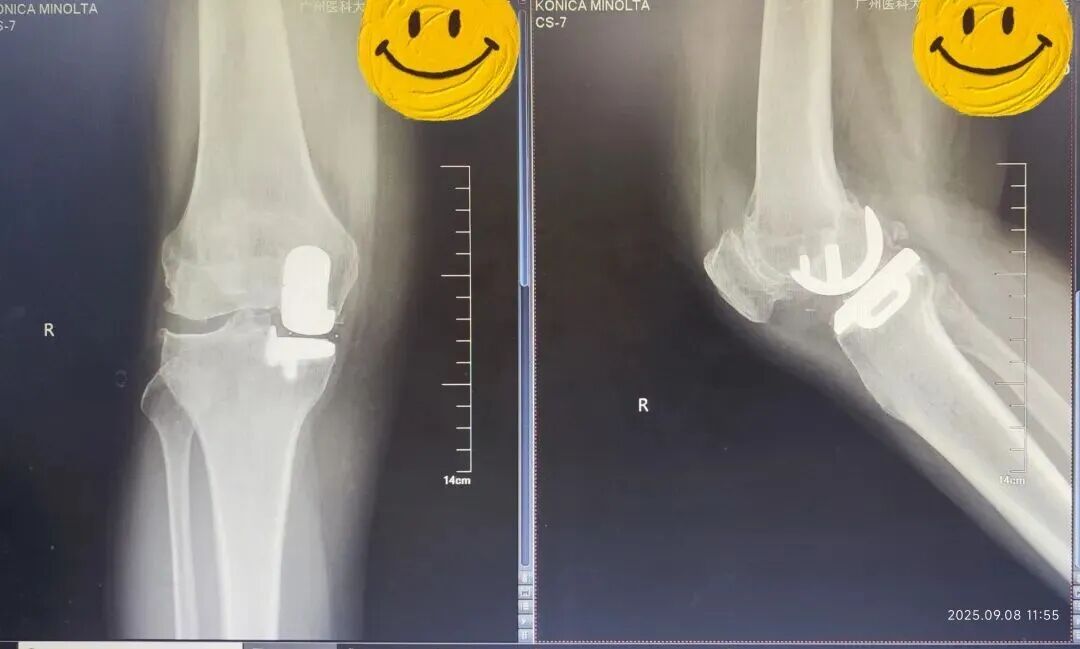

术前(左)术后(右)X线光片对比

“与全膝关节置换相比,部分置换创伤更小、出血少、恢复快,更重要的是能够保留患者自身的韧带和健康骨组织,维持更自然的膝关节功能。”陈东峰解释道。

在麻醉科配合下,陈东峰手术团队清除了增生的滑膜组织,去除了骨赘,对关节进行了适当松解,术中发现关节面磨损严重,软骨下骨暴露,内侧半月板后角脱位。医生精心安置了人工关节假体,替代了已经损坏的关节面。

手术后无需放置引流管,多模式镇痛下,患者麻醉恢复后即可下地完全负重行走,温女士终于摆脱了困扰她十年的膝痛问题。